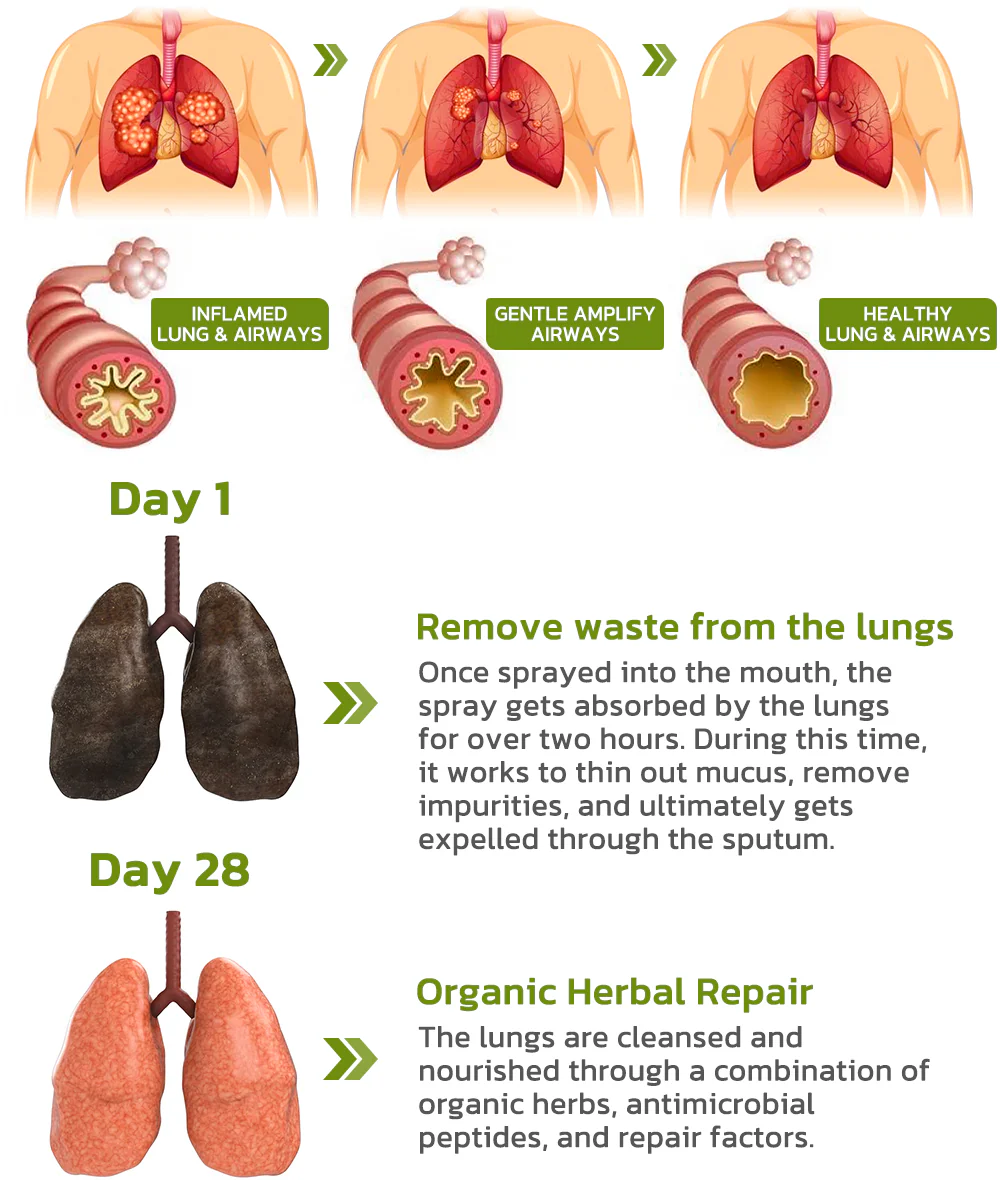

Continuous Use For More Than 28 Days

The mechanism of the HZA™️ BreathDetox Herbal Lung Cleansing Spray involves delivering a fine mist directly into the passages and airways, ensuring optimal effectiveness and targeted action. When you apply the spray into your mouth, it releases a gentle and precise mist that coats your respiratory system. This targeted approach enhances the product’s overall performance in promoting lung health and cleansing the respiratory system.